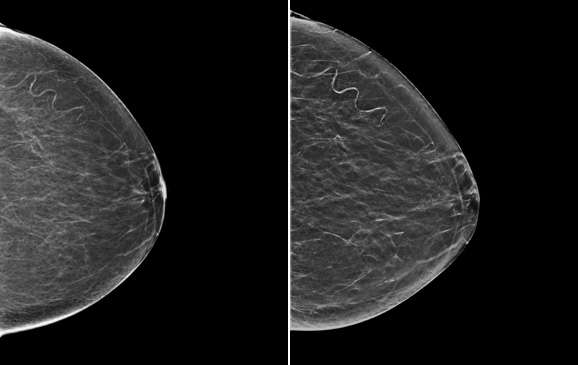

Traditionally, 2D mammograms have been performed, which offer a two-dimensional image of the breast. Screening mammograms are usually performed in two standard views, the craniocaudal (CC) and the mediolateral oblique (MLO) views. Additional diagnostic views including spot compression or variant angles may also be obtained. The differential attenuation characteristics of tissue allow for the identification of masses, calcifications, and other findings. For example, mammography can demonstrate suspicious microcalcifications that may otherwise not be palpable. Both screen film and, more recently, digital mammography formats have utilized 2D imaging.

Digital breast tomosynthesis (DBT), colloquially known as 3D mammography, is a newer technology that was approved by the FDA in 2011. DBT acquires multiple mammographic projections serially along an arc and reconstructs this data via post-processing techniques into thin slice images to create a quasi-three-dimensional assessment of the breast. These reconstructed images result in partial blurring of features outside the selected plane. The multiple thin images allow radiologists to scroll through each image separately and attenuates the pitfall of superimposed breast tissue in a conventional 2D mammogram.